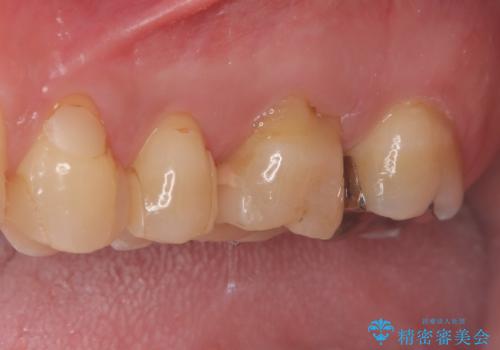

メタルインレーを丁寧に除去し、歯の状態を確認。その後、精密な形成を行い、適合性の高いセラミッククラウンを装着しました。セラミッククラウンは天然歯に近い見た目で、美しさだけでなく強度や機能性にも優れているため、患者様にも「自然な仕上がりで違和感なく噛める」と大変ご満足いただきました。

左上7のメタルインレーを除去|セラミッククラウンで自然な美しさと機能回復